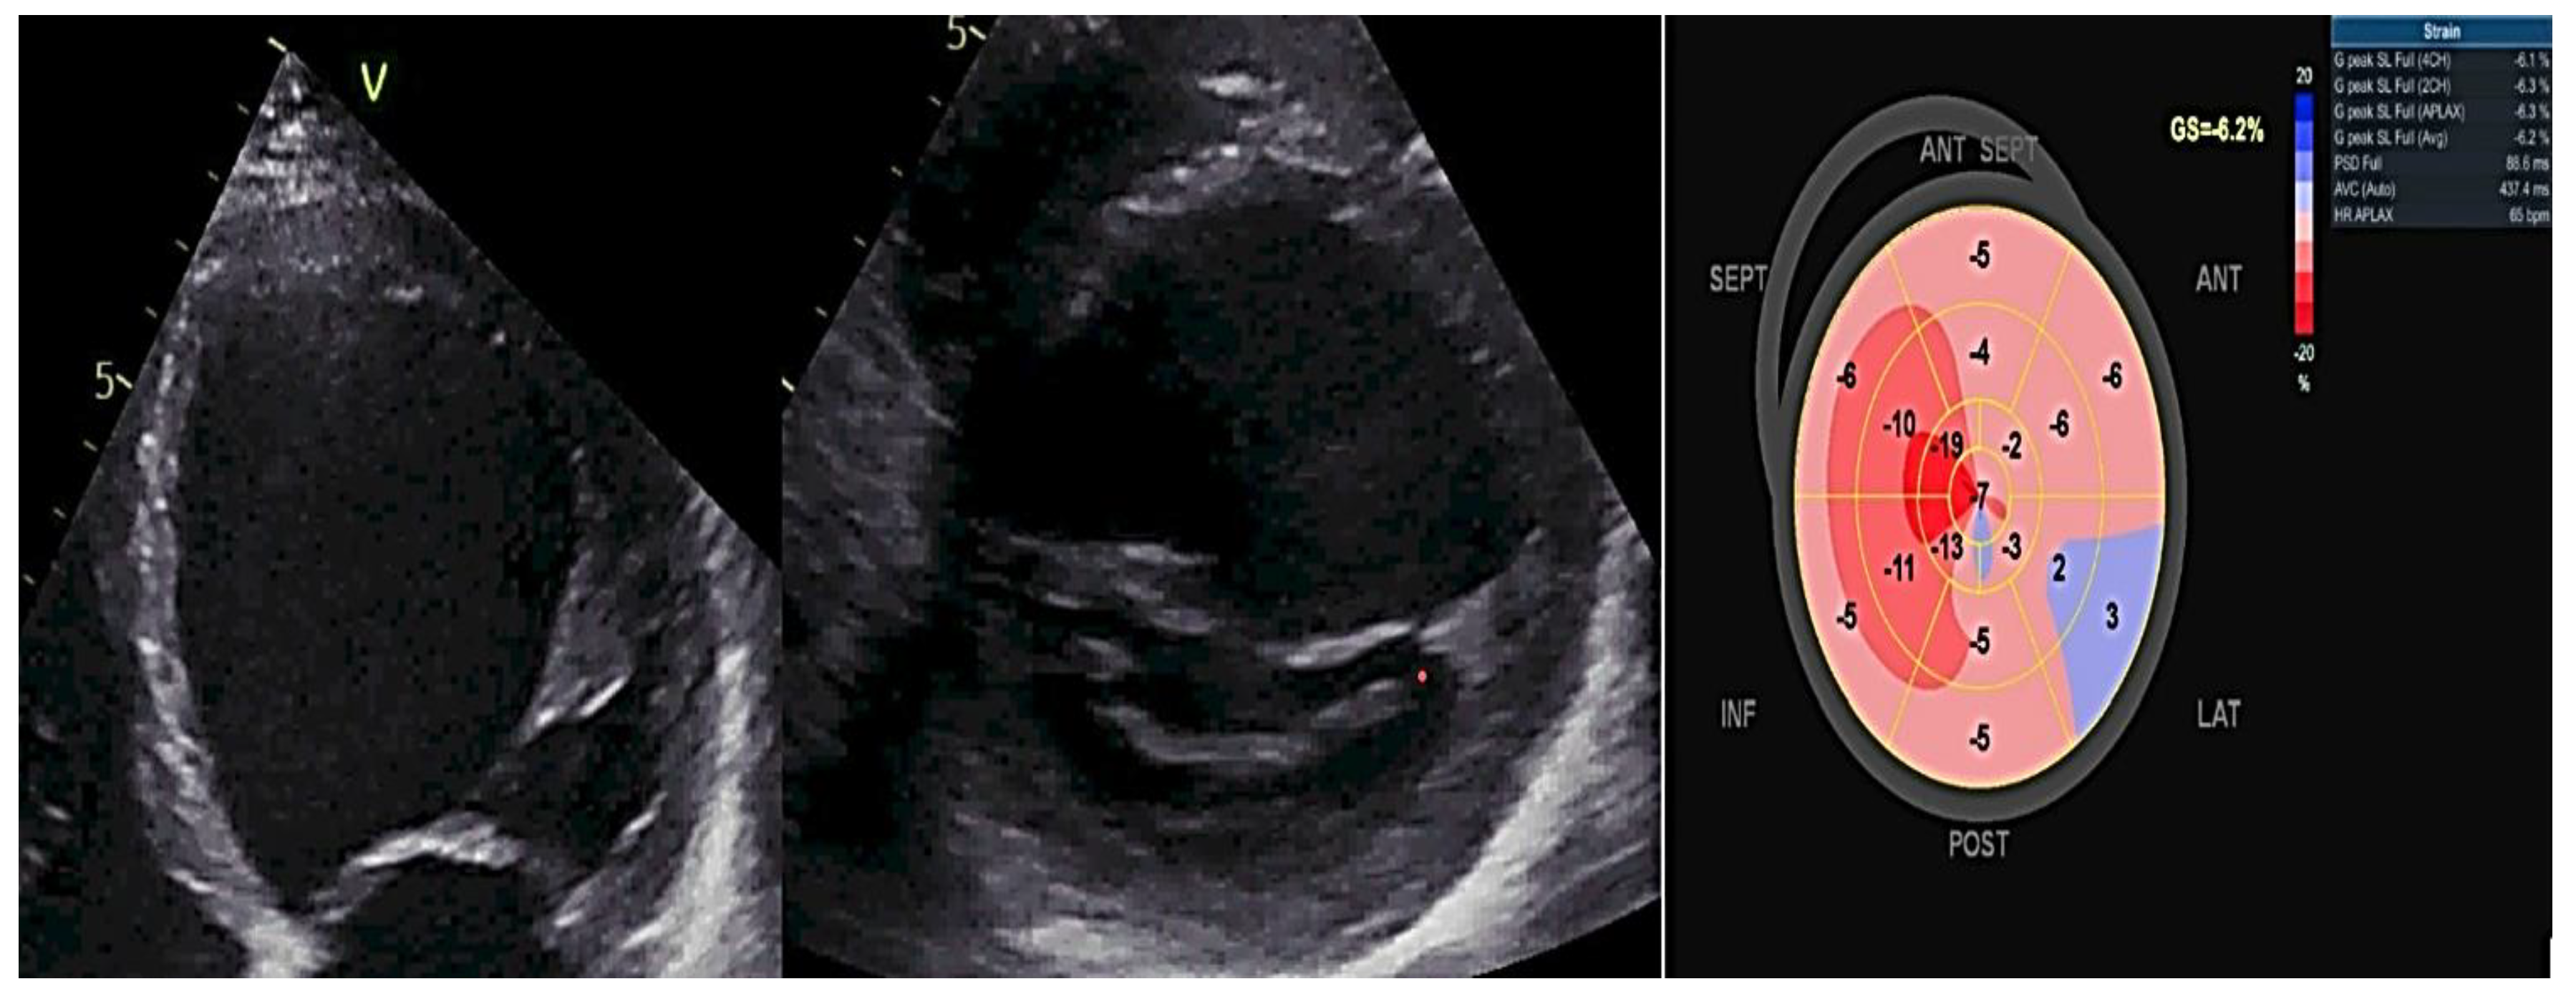

Regular screening, including clinical evaluation, electrocardiogram (ECG), and transthoracic echocardiography (TTE), should begin in adulthood or earlier if there are treatment implications [63]. The frequency of screening can range from every six months to every five years, depending on the existence or not of high-risk indicators and the usual age at which the illness typically appears in the family [60, 63]. LV dilatation on TTE in asymptomatic relatives might indicate subclinical illness, incidental illness, or physiological modifications. It is difficult to differentiate between these conditions, and since there is no dependable method to identify those who may develop obvious illness, regular surveillance is required. Currently, the screening criterion in TTE continues to be the LV size and ejection fraction. However, continuing research is being conducted to explore alternative preclinical indicators. Recently, researchers have assessed global longitudinal strain of the LV and observed a decrease in patients who are genotype-positive but phenotype-negative, compared to genotype-negative controls. Yet, the exact significance of global longitudinal strain in detecting or monitoring subclinical FDCM has not been determined [5]. Myocardial deformation imaging, specifically using speckle tracking or tissue Doppler, is a more sensitive indicator than EF (ejection fraction) for detecting subtle ventricular dysfunction. This is particularly useful in cases such as genotype-positive HCM (hypertrophic cardiomyopathy), DCM, and ARVC (arrhythmogenic right ventricular cardiomyopathy) in family members. Additionally, it can assist in distinguishing between different causes of hypertrophy, such as amyloidosis, HCM, and athlete's heart. Mechanical dispersion serves as an indicator of unevenness in contraction and draws attention to subtle structural alterations that would go unnoticed by alternative methods [64-67]. Figure 3 exemplifies a patient with FDCM examined by two-dimensional (2D) transthoracic conventional echocardiography and by 2D- speckle-tracking echography, showing dilated heart chambers, severe LV dysfunction (LVEF of 30%) and a Bull's eye myocardial deformation pattern with overall segmental low peak longitudinal strain values.